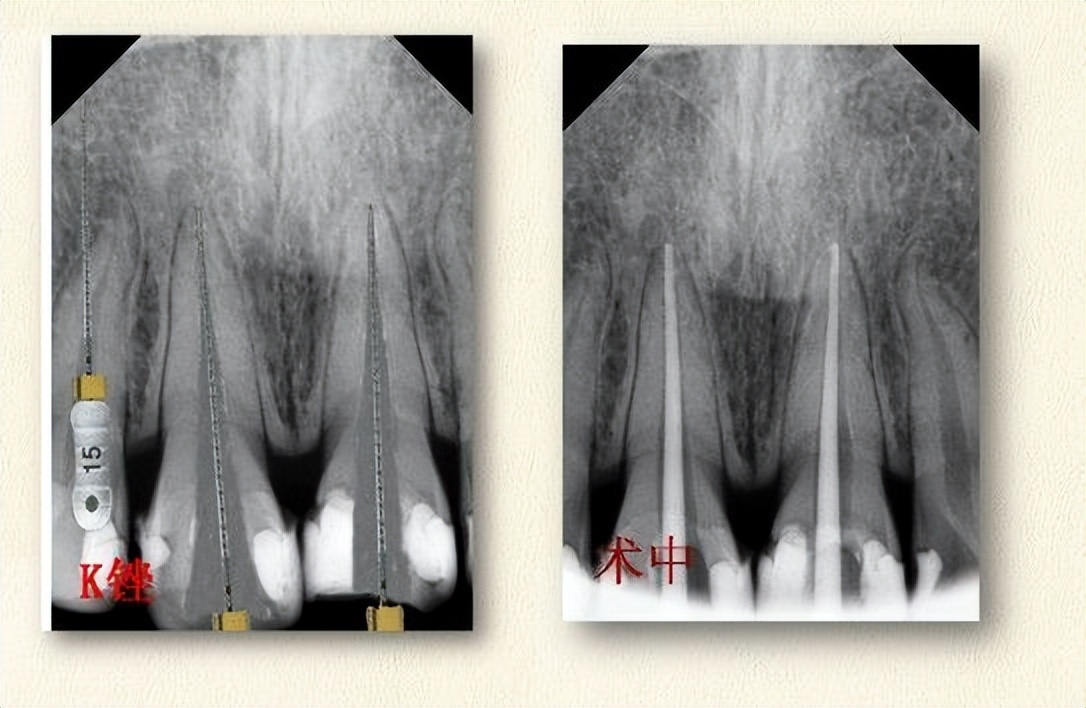

说到做冠,一般是损伤很大,伤及牙神经的牙齿,只要伤到牙神经,这颗牙齿大概率是要做根管治疗的,因为牙神经损伤基本不可逆,不做治疗以后疼起来会很麻烦!!!

前牙根管治疗费用300到600不等,地区不同,医院不同,价格不一样。

(根管治疗如上图,白色的柱状充填物是牙胶尖,用来封闭根尖孔的)